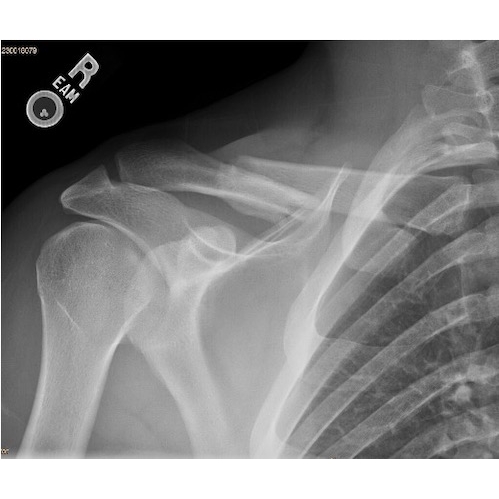

X-ray clavicle (Initial): Overlapping fracture middle one third right clavicle. Case Photo #1

X-ray clavicle (at 10 months): Healing fracture with overlapping ends. [Photo2]